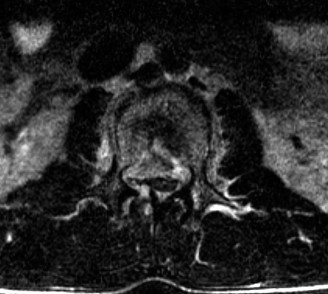

Prognosis of central cord syndrome? Indications for surgery for this disorder? CASE 2 A 56-year-old man presents to you with a chief complaint of severe right buttock, posterior thigh, and lower leg pain for 12 weeks. It radiates to the lateral aspect of his foot, and it is worse with sitting or standing for prolonged periods and with walking. Now over the past 2 weeks, he reports difficulty with toe push-off on the right side. Treatment so far has been nonsteroidal anti-inflammatory drugs (NSAID), physical therapy, and an epidural injection without significant relief. Physical examination findings include 4/5 right ankle plantar flexion, a positive straight leg raise on the right, and an absent right Achilles tendon reflex. Images of his lumbar spine are shown in Figures 1–4 and 1–5.

Figure 1–4

Figure 1–5

The correct answer is (C). The patient presents with classic right S1 radiculopathy and new onset plantar flexion weakness. The images demonstrate a right-sided paracentral disc herniation at L5/S1 compressing the traversing S1 nerve root. Despite nonoperative management, he continues to have severe pain and new weakness. Continued physical therapy or an epidural injection is unlikely to improve the patient’s pain at this time. In the setting of neurological decline, surgery is more strongly indicated. Lumbar discectomy is the most appropriate procedure for this patient. Fusion would only be indicated if there were radiographic signs of instability, which are not present.